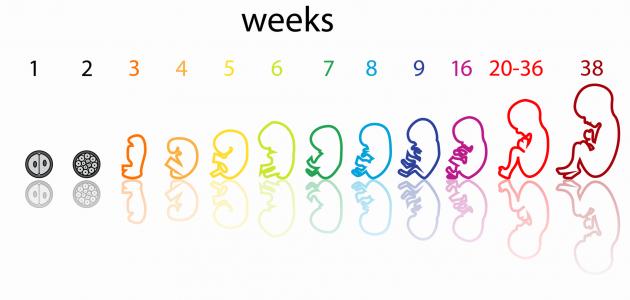

يستمر الحمل (بالإنجليزية: Pregnancy) النموذجي 40 أسبوعًا تقريبًا؛ تبدأ من اليوم الأول من آخر دورة شهرية حتى الولادة، وتُقسم لثلاث مراحل أو فصول ينمو ويتطوّر فيها الجنين بطريقة معينة،[١] فيبدأ الفصل أو الثلث الأول من الأسبوع الأول من الحمل وينتهي بانتهاء الأسبوع الثالث عشر، ويتبعه الثلث الثاني الذي يبدأ من الأسبوع الرابع عشر ويستمر إلى حوالي الأسبوع السادس والعشرين، ثمّ ينتهي بالثلث الثالث الذي يمتدّ حتى الولادة أي الأسبوع الأربعين،[٢] وفيما يأتي بيان لهذه الفصول بشيء من التفصيل:

فيما يأتي بيان مراحل تكون الجنين بالأسابيع الخاصة بالثلث الأول من الحمل:

- الأسبوع الأول: وفيه يستعد الجسم للحمل من خلال زيادة سمك بطانة الرحم (بالإنجليزية: Uterus) ليتمكن من إيواء البويضة المخصبة وتغذيتها بمجرّد انغراسها في بطانته، لذلك لا يُعد هذا الأسبوع جزءًا رسميًا من الحمل، ولكن تسهيلًا لحساب عمر الحمل فإنّ الطبيب يتتبع الحمل وموعد الولادة اعتمادًا على اليوم الأول من آخر دورة شهرية للمرأة.[٢]

- الأسبوع الثاني: يحدث التبويض (بالإنجليزية: Ovulation) بداية هذا الأسبوع، وتُخصّب البويضة بعد تقريبًا 12-24 ساعة من قبل الحيوان المنوي، وبمجرّد تخصيبها تبدأ بالانقسام إلى خلايا متعددة من خلال سلسلةٍ من العمليات المعقدة، ويكون ذلك أثناء انتقالها إلى أسفل قناة فالوب، ثمّ تدخل الرحم وتبدأ بالانغراس في بطانته.[٣]

- الأسبوع الثالث: وفيه تنزرع أو تنغرس البويضة المخصبة في بطانة الرحم الغنية بالمواد الغذائية، وتسمّى حينئذٍ الكيسة الأريمية أو الكبسولة البلاستوليّة (بالإنجليزيّة: Blastocyst)، إذ تكون ككرة صغيرة جدًا تتكون من مئات الخلايا التي تتكاثر بسرعة وتتطور إلى جنين، ولإيقاف المبيضين عن إطلاق المزيد من البويضات لاحقًا تُنتج هذه الخلايا هرمون الحمل (بالإنجليزية: Pregnancy hormone) المعروف علميًا بهرمون موجهة الغدد التناسلية الميشمائية البشرية واختصارًا hCG.[٣]

- الأسبوع الرابع: يكون الجنين الآن قد التصق بجدار الرحم، وتستمرّ الخلايا بالانقسام التي ستُكوّن أعضاؤه في الفترة القريبة، وقد يمكن رؤيته بالموجات فوق الصوتية لكن يكون بحجمٍ أصغر من حبة الأرز، ويبدأ هنا تشكّل الكيس الأمنيوسي أو ما يُعرف بكيس الحمل (بالإنجليزية: Amniotic sac) وهو أشبه ما يكون بوسادة مملوءة بسائل تحيط بالجنين وتحميه أثناء نموّه، ويكون الكيس متصلًا بالكيس المحّي أو الحويصلة السرية (بالإنجليزية: Yolk sac) ليُمدّ الجنين بالمواد الغذائية خلال الأسابيع الأولى.[٢]

- الأسبوع الخامس: قد يكون من الممكن ملاحظة نبض قلب الجنين خلال الموجات فوق الصوتية، لكن لا يمكن سماعه في هذه المرحلة، وباستمرار نموّ الجنين تبدأ الأم بالشعور بأولى أعراض الحمل كألم الثدي، وغثيان الصباح والحاجة المتكررة للتبول، ومن الجدير بالذكر أنّ الجنين في هذه المرحلة يتكون من ثلاث طبقات متميزة تتطوّر مع مرور الوقت لتشكّل فيما بعد أعضاءه وأنسجته، وهذه الطبقات هي:[٢][٤]

- الأسبوع السادس: في نهاية الأسبوع السادس سوف يكون حجم الجنين قد تضاعف ثلاث مرات، وستتشكل نصفا الكرة الدماغية، كما يمكن الآن تسجيل موجات الدماغ، أمّا عن القلب فينبض بانتظام بمعدل 150 نبضة تقريبًا في الدقيقة أي بما يعادل ضعف متوسط معدل ضربات قلب البالغين، لكن لا يزال النبض ضعيفًا لذلك لا يمكن سماعه بسماعة الطبيب.[٤]

- الأسبوع السابع: ينمو دماغ الجنين في هذه المرحلة بشكل أكثر تعقيدًا، وقد يمكن للطبيب رؤيته بوضوح داخل الجمجمة الشفافة، وفي الواقع تنمو الخلايا العصبية في هذه المرحلة بمعدّل مذهلٍ قد يصل إلى 100,000 خلية في الدقيقة، إضافةً إلى ذلك تتطوّر في هذا الأسبوع ملامح وجه مميزة للجنين، إذ تدلّ البقع الداكنة على مكان العيون وفتحات الأنف، كما يبدأ تشكّل جزء بسيط من الفم والأذنين أيضًا.[٤]

- الأسبوع الثامن: تحدث تطوّرات عديدة تتمثل بالآتي:[٥]

- +’الأسبوع التاسع:’ وفيه يكون القلب تقريبًا قد انقسم إلى أربع حجرات وجميع الأعضاء الأساسية للجنين في مكانها الصحيح إلى حدّ ما، وبنهاية هذا الأسبوع سيصبح حجمه بحجم حبة العنب إذ سيصل طوله حوالي 2.3 سنتيمترًا ووزنه حوالي 2 جرام، ومع اقتراب ذيل الجنين بالاختفاء سيبدو بشكل الإنسان أكثر، وستحدث التطورات الآتية لديه:[٦]

- الأسبوع العاشر: في الأسابيع الماضية كان الجنين في مرحلته الجنينية التي تتكون فيها الخلايا اللازمة لتشكل أعضائه الرئيسة وأطرافه ودماغه وجهازه العصبي، وسينتقل في هذا الأسبوع إلى مرحلة ينمو فيها بشكل واضح ومستمرّ إلى أن يصبح جاهزًا للخروج من الرحم، وفي هذا الأسبوع سينكمش الكيس المحي الذي كان يزود الجنين بالعناصر الغذائية قبل نمو المشيمة، ويُشار إلى بلوغ وزنه هنا حوالي 4 جرام، وطوله حوالي 3.1 من الرأس إلى الردف، بحيث يكون بحجم حبة الزيتون الأخضر تقريبًا، وستُلاحظ التطورات الآتية على الجنين:[٧]

- الأسبوع الثالث عشر: يصبح الجنين في هذا الأسبوع قادرًا على وضع إبهامه في فمه، ويومًا بعد يوم يبدو وجهه أكثر شبهًا بالإنسان، إذ تنتقل عيناه من جانبي رأسه إلى مقدمه وجهه، وقد تظهران بلون أزرق أو بنيّ أو أخضر، وتنتقل أذناه إلى مكانهما، وينمو جذعه بشكلٍ أسرع، كما يزداد طول ذراعيه ليتناسب أكثر مع جسمه.[٤]

مع بداية الثلث الثاني يكون حجم الجنين ما زال صغيرًا، ومن الجدير بالذكر أنّه بتخطي الشهور الثلاثة الأولى يقل خطر التعرض للإجهاض (بالإنجليزية: Miscarriage)، وتبدأ أعراض الحمل المبكرة التي عانت منها الحامل كالتعب وغثيان الصباح بالاختفاء، وقد تشعر بأنها أكثر نشاطًا فيصبح باستطاعتها ممارسة التمارين الرياضية بعد الرجوع لطبيبها لأخذ المشورة الطبية حول الرياضة المناسبة للحامل عامّةً ولحالتها الصحية خاصةً،[٣] وفيما يأتي بيان هذه المرحلة من الحمل بالتفصيل: